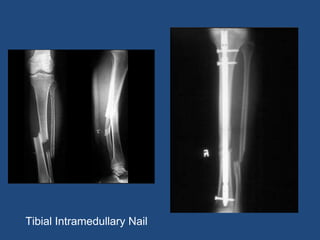

Tibial Intramedullary Nail

Tibial Intramedullary Nailing •Indications - Most adult tibial shaft fractures - Approach - Parapatellar - Suprapatellar

Tibial Intramedullary Nailing •Proximal fractures have high incidence of deformity • Due to pull of muscular insertion points